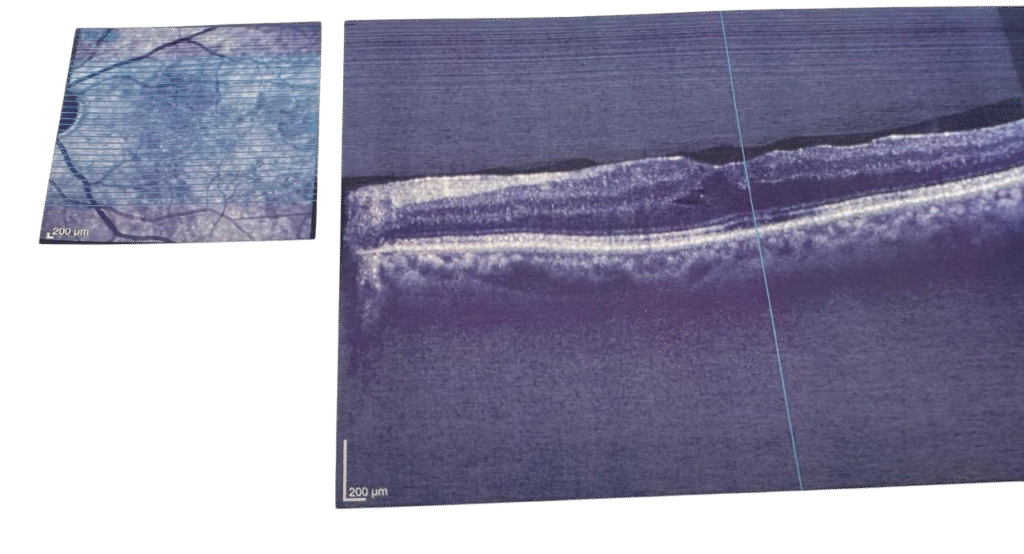

Resim 1: Epiretinal öncesi

Resim 2: Epiretinal sonrası